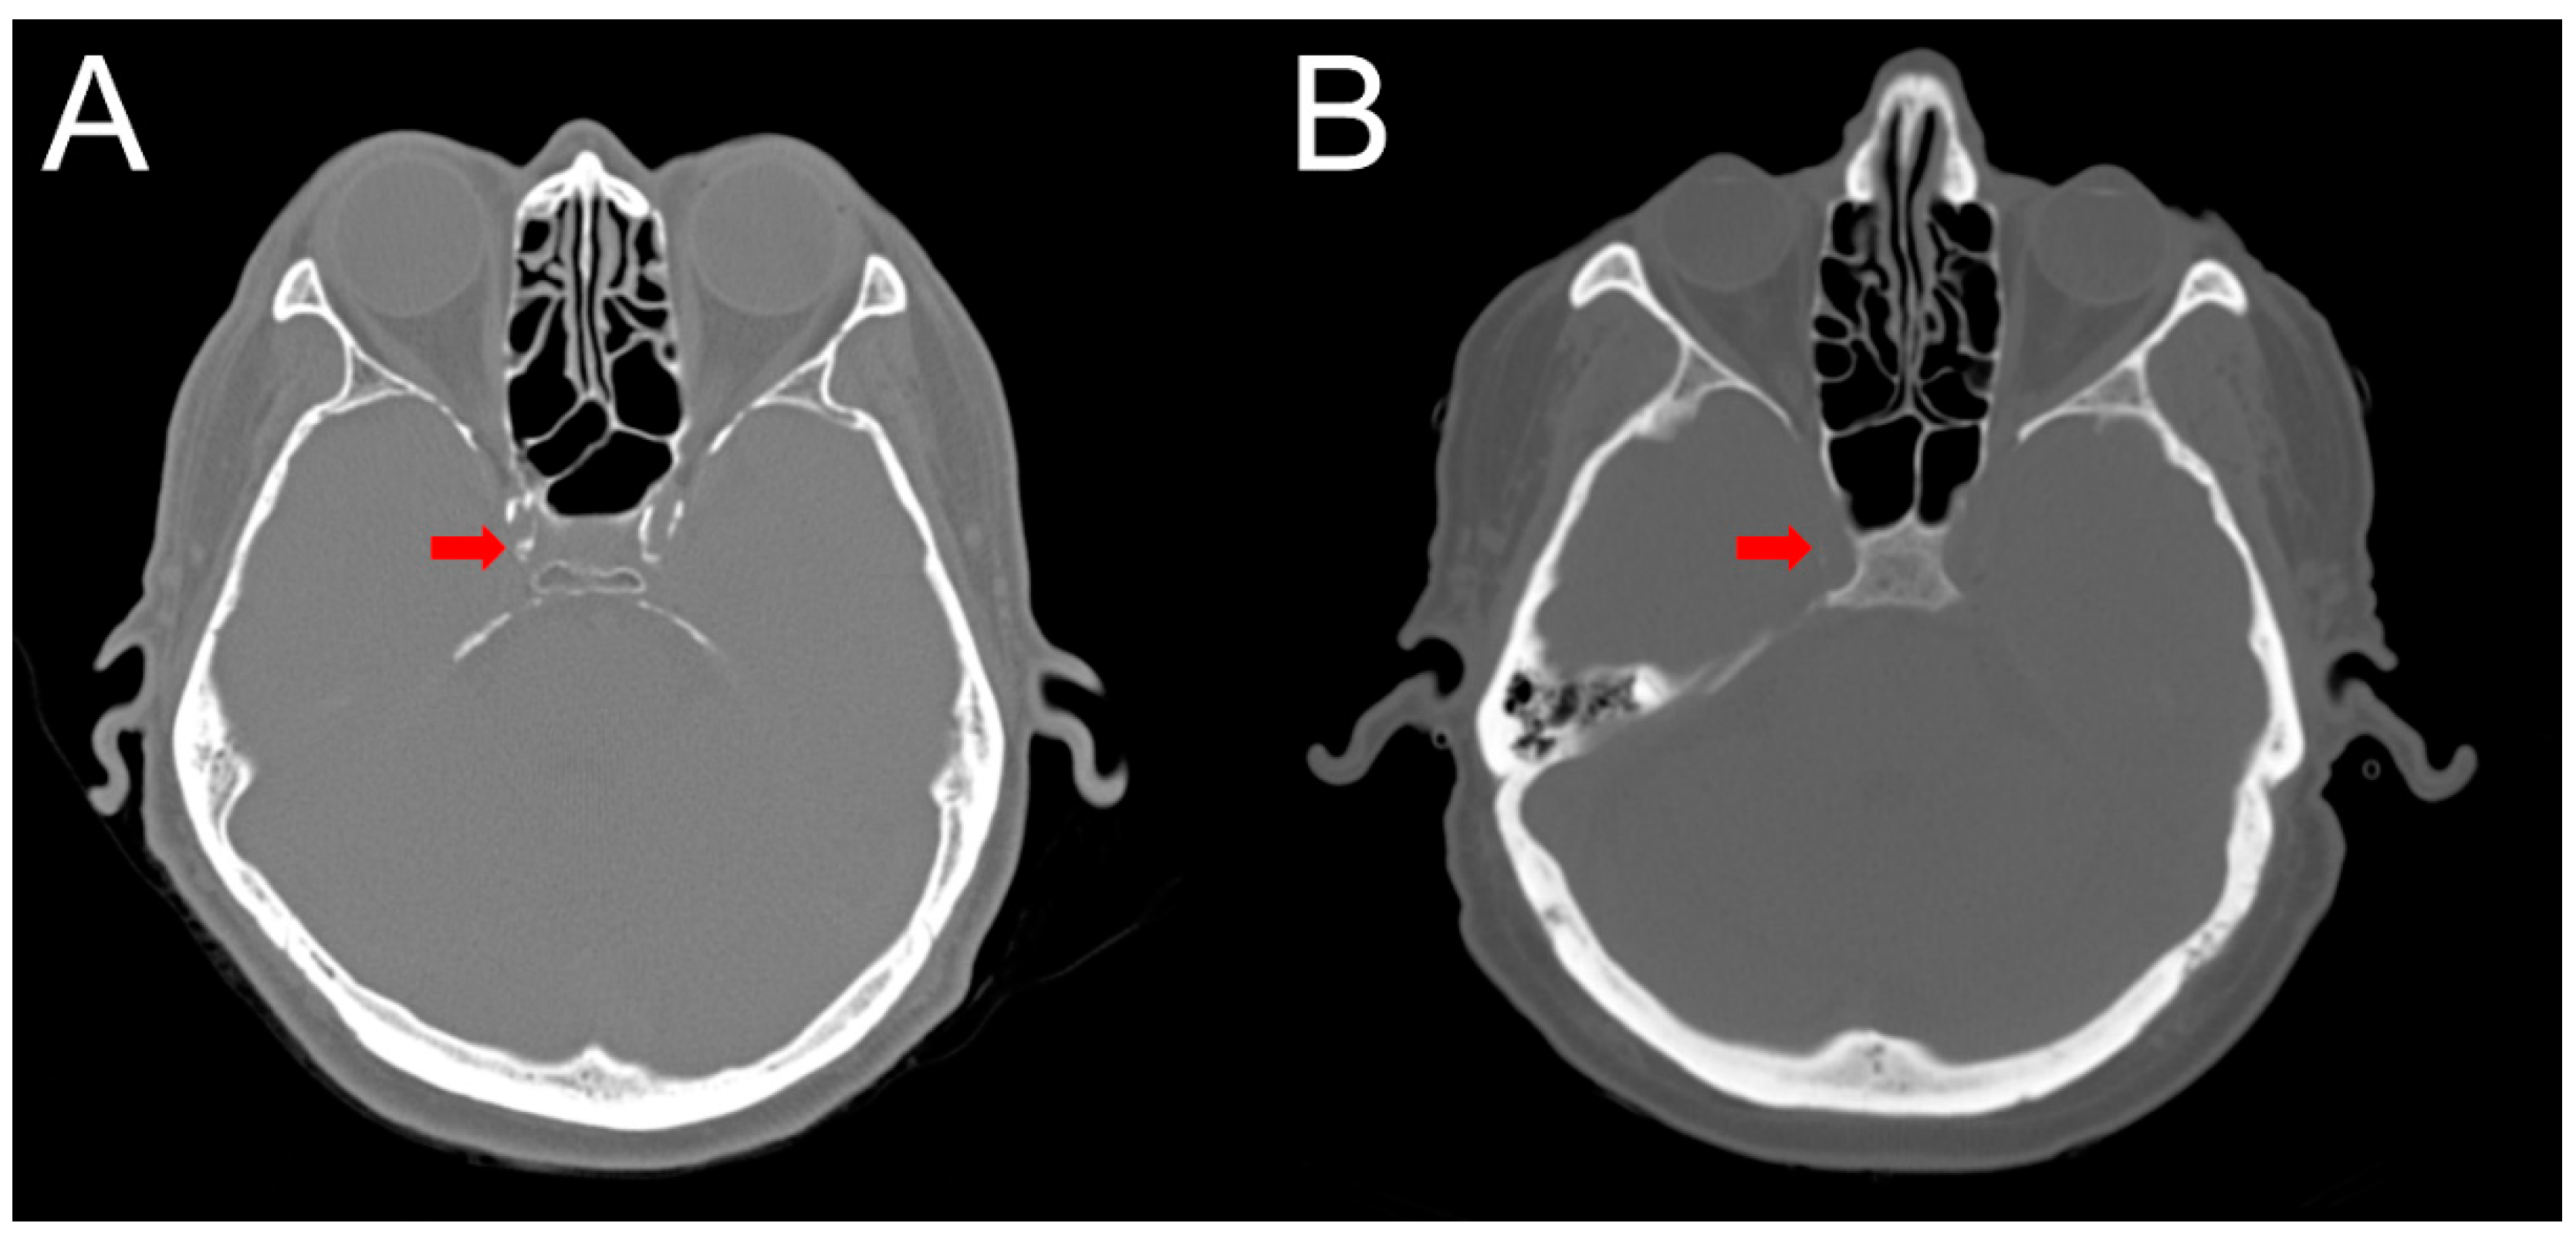

2.4. Intracranial Calcification

4.4. Computed Tomography (CT) Interpretation and Cerebral Arterial Calcification Score

4.5. Clinical Outcomes